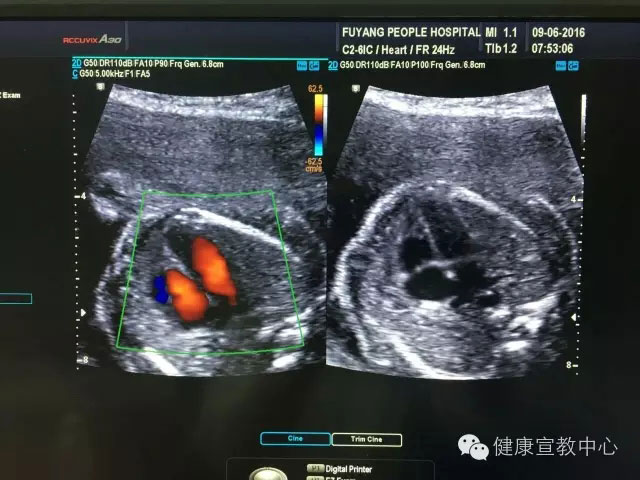

胎兒專項(xiàng)系統(tǒng)檢查是建立在胎兒中孕系統(tǒng)超聲檢查的基礎(chǔ)上對所篩查的器官、作更系統(tǒng)化精細(xì)化檢查。從2015年,開展胎兒專項(xiàng)系統(tǒng)篩查(胎兒心臟、胎兒中樞神經(jīng)系統(tǒng)、顱腦微小畸形、脊柱等)以來,共計(jì)完成400余例。目前,該項(xiàng)技術(shù)處于省內(nèi)領(lǐng)先水平,部分省級醫(yī)院還尚未開展。

(胎兒超聲心動(dòng)圖)